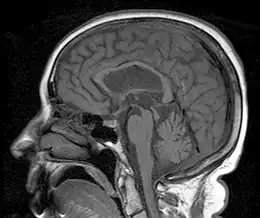

| In PSP the midbrain (red) to pons area (blue) ratio is typically reduced to 0.12[3] | |

MRI is often done to diagnose PSP. MRI may show atrophy in the midbrain with preservation of the pons giving a "hummingbird" sign appearance and Mickey Mouse sign.[32]